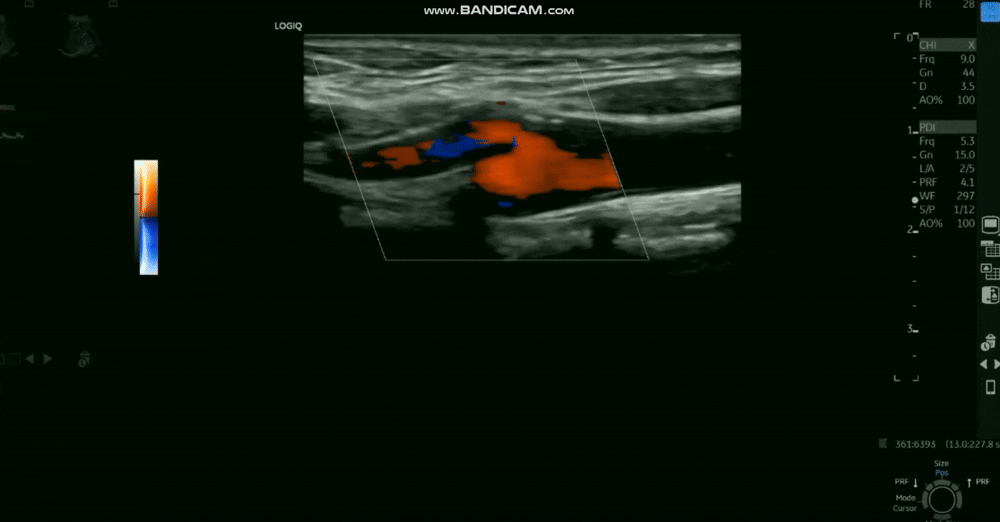

На экране это выглядит как:

• Цветное допплеровское картирование — красные и синие зоны, показывающие направление и скорость потока крови.

• Спектральный допплер — график, позволяющий точно измерить скорость кровотока, индекс резистентности и другие параметры.

Аппарат GE Logiq E10 R3 позволяет не просто увидеть цветные пятна, но и автоматически рассчитать ключевые параметры гемодинамики по допплеровскому спектру: скорость кровотока, индекс резистентности (сопротивление сосудов), пульсационный индекс. Эти цифры — основа для точного диагноза.